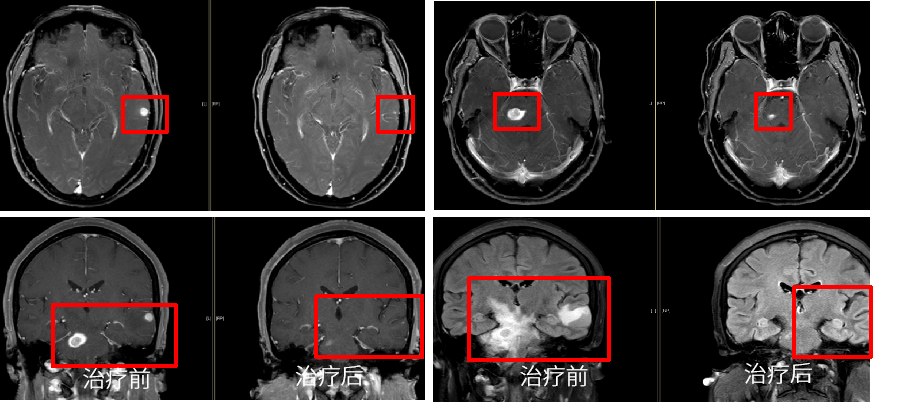

肺癌是严重威胁人民群众生命健康的恶性肿瘤,晚期肺癌患者已错失最佳手术时机,传统的化疗方案对于晚期肺癌患者的总体效果难以满足临床需求[1]。近年来,以PD-1/PD-L1抑制剂为代表的免疫疗法在肺癌治疗中的价值得到积极探索,我国自主研发的PD-1抑制剂替雷利珠单抗在肺癌领域也进行了广泛布局,目前已获批晚期非小细胞肺癌(NSCLC)一线及二/三线治疗适应症,且是唯一实现不可手术局晚及晚期NSCLC医保全程覆盖的PD-1抑制剂。 本期由中山大学孙逸仙纪念医院丁嘉萱医生为大家分享一例替雷利珠单抗用于晚期肺腺癌伴脑转移患者的诊疗过程,并由刘宜敏教授进行点评。该病例中,患者接受替雷利珠单抗治疗已实现超2年持续CR,目前免疫治疗已满两年,遂停止治疗,患者一般情况良好,后续定期影像学随访。 分享专家 丁嘉萱 医生 肿瘤学硕士 中山大学孙逸仙纪念医院放疗科医师 点评专家 刘宜敏 教授 病例详情 基本情况 一般情况:患者女性,53岁。 主诉:因“咳嗽伴气促4月,头痛半月”就诊。 现病史:患者咳嗽伴气促4月,头痛半月,于2020.05我院首诊。 既往史、个人史及家族史:无特殊。 月经婚育史:无特殊。 辅助检查 入院后基线评估: (1)胸部CT示:左肺门区可见一团块状影,大小约42.8mm*30.0mm,边界清,增强扫描呈轻度强化,强化尚均匀,病变包埋左下肺动脉,左肺下叶支气管狭窄,病变下缘可见子灶。纵隔内结构清楚,后纵隔内可见一团块状影,大小约52.8mm*21.0mm,边界清,强化方式与上述病灶相仿,与食管分界不清。双侧肺门淋巴结转移。 入院后胸部CT检查 (2)头颅MRI示:左颞叶、脑干见结节状稍长T1、稍长T2信号影,DWI呈稍高信号,增强后明显强化,周围见片状水肿影,直径分别为8.7mm和11.2mm;左颞叶、脑干异常信号灶,结合病史,考虑转移瘤;全腹MR和全身骨显像无明显异常。 入院后MRI检查 (3)超声支气管镜引导下的经支气管针吸病理活检(EBUS-TBNA):1、左上叶下舌段支气管及左下叶背段支气管,左下叶基底段支气管管腔外压性狭窄;2、隆突增宽;3、纵隔淋巴结转移(第7组,第11L组),EBUS-TBNA细胞病理提示为肺来源腺癌。 于左侧第二隆突探及第11L组淋巴结行EBUS-TBNA (4)免疫组化:TTF-1(+)、NapsinA(+)、CK7(+)、CK5/6部分(+)、Ki67约25%(+),P40(-),PD-L1(22C3)肿瘤细胞约30%(+)、PD-L1(22C3)免疫细胞约20%(+)。 (5)基因检测:RET基因重排。 临床诊断 左肺腺癌伴脑转移(T4N3M1c,IVB期);RET基因重排 诊疗经过 于2020.06.01、2020.06.22、2020.07.13、2020.08.04、2020.08.25、2020.09.15予替雷利珠单抗200mg+培美曲塞800mg+奈达铂110mg治疗6周期;期间于2020.06.04-2020.07.13行WBRT(37.5Gy/15f)+SRS(14Gy),WBRT同期给予替莫唑胺(75mg/m2)。 免疫治疗2周期后复查胸部CT提示:左肺门区肿块较前缩小(21*14mm),后纵隔淋巴结较前缩小(22mm*9mm),左颞叶病灶基本消失、脑干病灶明显缩小(5mm),水肿明显消退。疗效评估为PR。免疫治疗4周期后复查胸部CT,疗效达到CR。 治疗前vs. 免疫治疗2周期后复查胸部CT结果对比 治疗前vs. 免疫治疗2周期后复查胸部CT结果对比 治疗前vs. 免疫治疗4周期后复查胸部CT结果对比 后暂停免疫联合化疗,于2020.09.17-2020.10.30行肺癌累及野放疗(pGTV、pCTV:60Gy/30f)。后于2020.11.12-2022.08.25行替雷利珠单抗200mg+培美曲塞500mg维持治疗23周期。期间定期影像学随访(外院),疗效维持CR。 2021.11.17胸部CT提示:左肺下叶背段及左肺上叶近肺门区团片状密度增高影,其内支气管稍扩张,邻近胸膜可见增厚,同前大致相仿。右肺上叶纵隔旁至近肺门区亦见条片状实变影,部分沿支气管分布,局部支气管稍扩张;右肺中叶内侧段见少许条状影,同前大致相仿。少量心包积液较前稍增多,新见双侧胸腔少量积液。纵隔内见多枚小淋巴结。附见肝右叶后段低密度灶部分向外突出,肝脏余部另见低密度小结节,十二指肠降段见含气囊袋影,同前大致相仿。 2021.12.16头颅MRI(平扫+增强)提示:脑桥右侧区见一小条片异常信号影,T2W1及FLAIR上呈稍高信号,信号较前减低,T1W1上显示欠佳,增强扫描现片未见明确强化,余颅内脑组织形态、信号正常,中线结构居中,脑室系统形态、大小正常,脑池、脑沟及脑裂未见异常,小脑未见异常信号。增强后脑组织强化正常,未见异常信号灶。附见:双侧筛窦及右侧上颌窦黏膜少许增厚。 2022.06.23 PET-CT检查提示:1、左肺癌治疗后,左肺下叶背段及左肺上叶近肺门区斑片状密度增高影伴轻度代谢增高,病灶较前明显吸收,代谢较前减低,考虑放射性肺炎较前吸收、好转,建议追踪复查;2、左侧肺门(10L)及纵隔内(4R、5、7 组)多个小巴结,代谢未见明显增高,结合病史,考虑为淋巴结转移灶治疗后处于明显抑制状态,建议追踪复查;3、脑转移瘤治疗后,颅脑未见明显提示脑转移瘤的高代谢灶,结合病史,考虑脑转移瘤治疗后好转,请结合MRI增强结果。 患者接受免疫治疗满两年(末次治疗时间为2022.08.25),疗效维持CR,与患者充分沟通后,停止免疫维持治疗,定期随访。 2022.11.22头颅MRI(平扫+增强)提示:脑桥右侧区见一小条片异常信号影,T2W1及FLAIR上呈稍高信号,T2W1上显示欠佳,增强扫描未见明确强化,较前大致相仿。双侧顶叶及左基底节区异常信号灶。余颅内脑组织形态、信号正常,中线结构居中。脑室系统形态、大小正常,脑池、脑沟及脑裂未见异常。增强后余脑组织强化正常,未见异常信号灶。附见:双侧筛窦及上颌窦黏膜少许增厚。 2022.12.23胸部CT提示:双肺门区条片状实变影较前缩小、变淡,局部支气管通畅,增强扫描未见明确异常强化灶;右肺中叶内侧段见少许条状影,同前相仿。心包未见积液。纵隔及肺门未见肿大淋巴结;双侧胸腔未见积液。附见肝右叶后段低密度灶部分向外突出,最大横断面约4.4*2.5厘米,增强扫描呈早出晚归强化特点。肝脏余部另见低密度无强化小结节。十二指肠降段见含气囊袋影。 病程回顾 病例点评 该患者在完善相关检查后,最终被确诊为“左肺腺癌伴脑转移、后纵隔与双侧肺门淋巴结转移”。肺癌起病隐匿,约10%-25%的NSCLC患者在确诊时已发生脑转移,约50%的患者在疾病进展中发生脑转移[2]。肺腺癌作为NSCLC的主要病理类型之一,其发病率近年来持续上升[3]。 肺癌脑转移患者的死亡率很高,传统的治疗手段疗效非常有限。数据显示,在未接受治疗的脑转移患者中,中位OS仅为1个月,而接受最佳支持疗法的患者OS约为2个月[2]。近年来,免疫药物及靶向药物的研发问世,大大提高了肺癌脑转移患者的生存率。该患者PD-L1表达阳性,一项汇总分析结果显示[4],对于PD-L1 TPS≥1%的NSCLC脑转移(包括未经治)患者,相比单纯化疗,免疫治疗可改善治疗结局,同时具有更少的不良事件。 有研究表明[5],免疫联合放疗不仅可控制照射区原发肿瘤增殖,同时也能促进肿瘤组织释放抗原形成原位灭活疫苗增加免疫治疗疗效。在一项研究报道中,NSCLC脑转移患者接受免疫联合立体定向放疗安全性良好,不仅降低照射野外复发率,还可提高患者生存期[6]。此外,基因检测提示该患者存在RET基因重排,但我国首个高选择性RET抑制剂获批时间为2021年3月,在该患者2020年6月开始接受治疗时靶向药物暂不可及。 证据显示,免疫联合化疗具有协同增效作用[7],结合该病例具体情况及循证医学证据决定采用免疫联合化疗进行治疗。考虑到该患者为异地就医,为有效管理,提高患者依从性,需选择半衰期长的免疫药物,而我国自主研发的PD-1抑制剂替雷利珠单抗终末半衰期约为26天,达到同类药物最高范围,经MDT讨论予替雷利珠单抗联合化疗,并行WBRT+SRS(WBRT同期给予烷化剂)。近年来,替雷利珠单抗全面布局肺癌领域,积累了丰富的循证医学证据。 RATIONALE 304[8]为一项III期、多中心、随机、开放研究,旨在对比替雷利珠单抗联合化疗和单用化疗一线治疗晚期非鳞状NSCLC的疗效和安全性。在2022 ESMO IO大会上,RATIONALE 304研究公布了最新数据,中位随访16.1个月后,替雷利珠单抗联合化疗组的mPFS进一步延长至9.8个月,显著降低37%的疾病进展风险,ORR达到57.8%,其中CR率提升至4.9%,约为对照组的3倍;mDOR进一步提升至10.6个月,患者获益持久。同时,该研究在此次大会上首次更新了OS数据,联合治疗组的mOS达到21.6个月,HR为0.68,显著降低32%的死亡风险。此外,在RATIONALE 304研究[9]的事后分析中,首次探索了免疫治疗联合化疗的至缓解时间分布,旨在充分了解免疫治疗的反应特征、最大化免疫治疗的临床获益提供了全新思路。结果显示,替雷利珠单抗联合化疗治疗有近50%的应答者在第二次评估后(≥4周期治疗后)出现首次缓解,提示若首次肿瘤评估未达到肿瘤缓解,不必急于停药,继续治疗仍很有可能达到缓解;75%达到CR/PR的患者通过持续治疗,肿瘤会持续退缩,首次缓解到最大肿瘤缓解的中位时间为3.6个月(约5个周期),肿瘤缓解深度更深的应答者,其PFS有延长的趋势,提示已达到CR/PR的患者,持续治疗肿瘤可进一步缩小,实现更长PFS获益。 患者在接受替雷利珠单抗联合治疗2周期后快速达PR,4周期疗效达到CR。6周期后暂停免疫治疗,在针对肺癌累及野放疗后,继续予免疫联合化疗维持治疗23周期,考虑到患者耐受性,在保证疗效的基础上化疗药物(培美曲塞)由标准剂量减量至500mg,以提高生活质量,期间影像学随访疗效维持CR。该患者共接受替雷利珠单抗治疗29周期,截至发稿已实现超2年长生存,充分验证了其在真实世界中用于肺腺癌脑转移患者的有效性和安全性。 根据2020年V1版《NCCN 非小细胞肺癌临床实践指南》,如果患者一线应用免疫疗法,则应接受两年的免疫维持治疗[10],具体临床实践中免疫治疗满2年后继续用药也可持续获益。该病例中,患者自2020年6月开始免疫治疗,至2022年8月已满两年,与患者充分沟通后,停止免疫维持治疗。截至末次随访(2022年12月),患者一般情况良好,未来实现长期生存值得期待。 长期以来,生存期短、预后差的肺癌脑转移患者常被排除在临床试验之外,血脑屏障(BBB)及血液-肿瘤屏障(BTB)等特殊结构也给脑转移相关机制研究造成重重困难[2]。目前,免疫联合放疗还有许多亟待解决的问题,如疗效评价、治疗结合时机、放疗范围及剂量等[5]。期待在未来,该领域能有更深入的研究进展,造福万千肺癌脑转移患者! 参考文献: [1] 王渊, 谭盼, 等. 中国医院用药评价与分析. 2023,23(03). [2] 马力, 朱娅, 等. 中国医药导报. 2023,20(03). [3] 李芳, 韩采利, 等. 肿瘤防治研究. 2023,50(03). [4] Aaron S Mansfield, et al. JTO Clin Res Rep. 2021 Jul 1;2(8):100205. [5] 周冲, 韩亮, 等. 中华转移性肿瘤杂志,2022,05(4):340-343. [6] Kamran A Ahmed, et al. J Neurooncol. 2017 Jun;133(2):331-338. [7] 赵景景, 李玲, 等. 实用癌症杂志. 2022,37(06). [8] Shun Lu, et al. ESMO IO 2022: 138P. [9] Lu S , et al. CSCO 2022. [10] NCCN Guideline NSCLC 2020.V1.